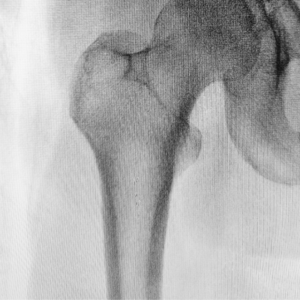

La radiografía de extremidades superiores o inferiores permite obtener imágenes de manos, muñecas, pies, rodillas y otras estructuras que se encuentren en brazos o piernas. Es ideal para detectar fracturas de hueso, otras lesiones y enfermedades articulares degenerativas en la rodilla.